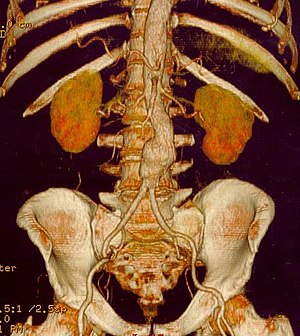

This is a review of the effects of

CKD on increased morbidity and mortality of abdominal aortic aneurysm repair. The abdominal

aorta has branches to the superior mesenteric

arteries proximally, and below that both renal arteries, which also supply the adrenals (suprarenal).

Severe atherosclerosis with plaque buildup and separation of the media from the endothelium, can migrate down the addominal aorta before frank rupture of an aneurysm. Abdominal aortic aneurysm often extends from below the the renal arteries, to the

internal spermatic vessels, or as far as the iliacs.

http://upload.wikimedia.org/wikipedia/commons/thumb/4/4a/Contrast-enhanced_CT_scan_demonstrating_abdominal_aortic_aneurysm.jpg/120px-Contrast-enhanced_CT_scan_demonstrating_abdominal_aortic_aneurysm.jpg

Abdominal Aortic Aneurysm in Computer Tomography (Photo credit: Wikipedia)